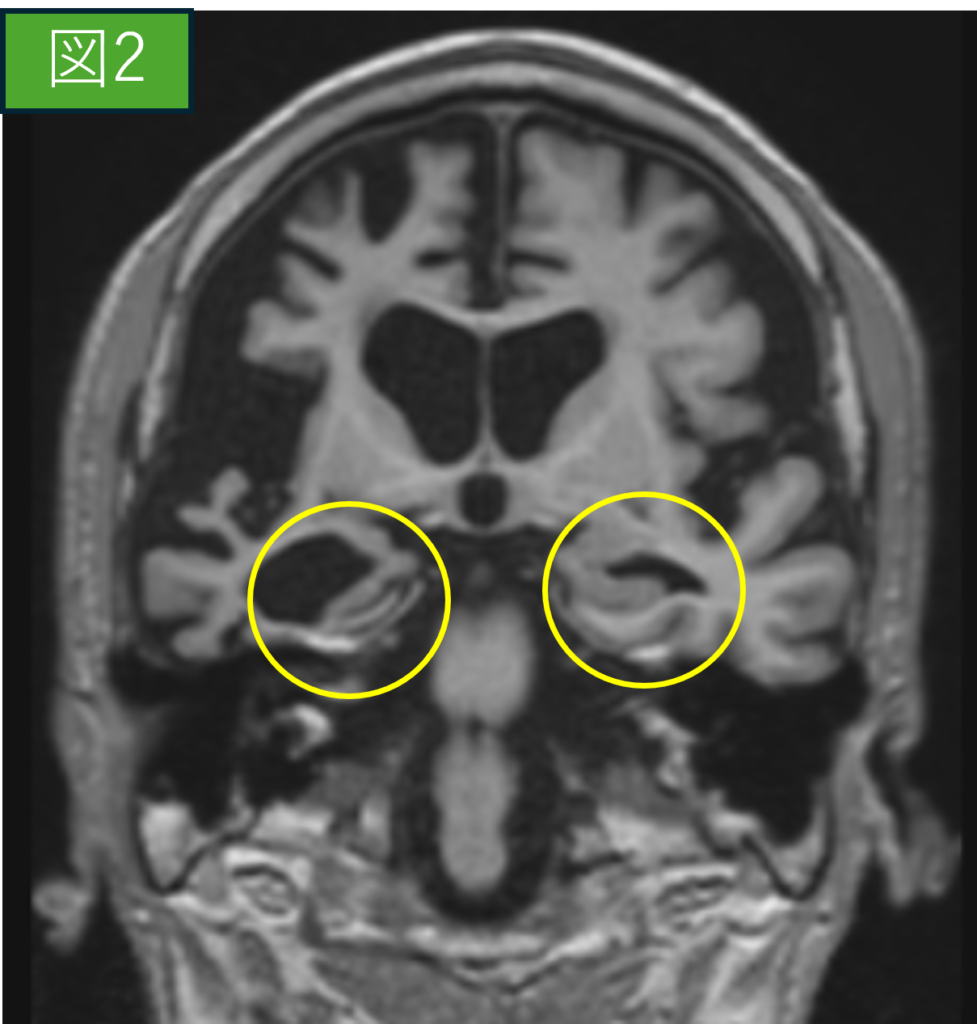

脳萎縮MRI画像(冠状断像)

症例画像から図1(正常画像)・図2(脳萎縮画像)

〇内が海馬を示しています。

正常の海馬は成人であれば6cm程の大きさであり、加齢や生活習慣によってはさらに小さくなります。図1と図2を比較すると脳全体の萎縮や海馬の萎縮も顕著に見られた症例です。